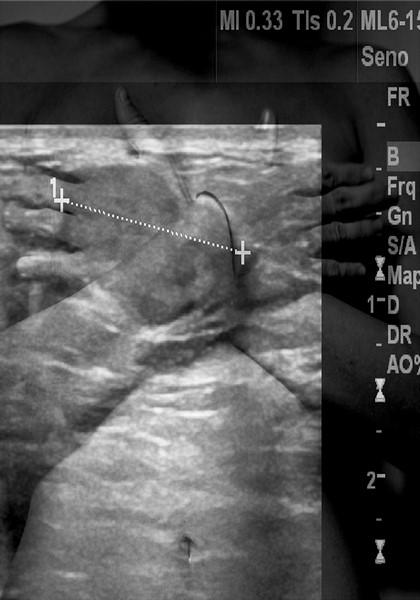

«Cecilia Del Gatto – scrive Daniele De Luigi – costruisce le proprie immagini come se fossero destinate a una campagna pubblicitaria o alle banche dati delle stock photos: inquadrature chiare, colori piacevoli, corpi ritratti in pose scultoree a compiere gesti semplici. I volti sono però avvolti in un reticolo di fili colorati che li benda completamente, rendendoli anonimi manichini. Se l’effetto è quello di fotografie fortemente ironiche e giocose, ne emerge però una riflessione pungente sulle crescenti difficoltà di affermare un’identità nelle relazioni con l’altro. Francesca Giannelli con “Newborders” ci conduce all’interno di uno spazio profondamente intimo per raccontare una difficile storia personale, quella che l’ha vista affrontare le cure per superare una malattia. Sovrapponendo a fredde immagini diagnostiche autoritratti fieri e palpitanti, la fotografa ci chiama a condividere il suo percorso di sofferenza che tuttavia trasforma in viaggio alla conoscenza di sé, alla scoperta del proprio corpo e della propria identità, i cui confini sono messi improvvisamente in discussione. Giulia Lazzaron si muove sul confine tra medium artistici sperimentando la fusione di grafica e fotografia. Al primo affida la creazione di forme organiche provenienti da un immaginario onirico ricco di simboli che attinge a un mondo interiore, realizzate con la tecnica incisoria. La fotografia costituisce lo scenario in cui questi elementi si muovono, ribaltando però la tradizionale funzione dei due strumenti: mentre le forme acquistano una strana consistenza reale, l’immagine fotografica sembra designare un ambiente irreale. Le immagini di Isabella Quaranta, suadenti e dal sapore onirico, si nutrono di fonti di ispirazione che spaziano dalla pittura simbolista al teatro, alla fotografia di moda. I cromatismi bruni e delicati e i giochi di sfocatura lasciano tuttavia trapelare una forte carica di energia vitale di cui si fanno portatrici le figure femminili, che delle immagini sono protagoniste. Proiezioni della vita intima, di sogni e paure, prendono forma in visioni di corpi sospesi, luoghi misteriosi e presenze enigmatiche che l’occhio e l’immaginazione di chi guarda è invitato a decifrare. La serie di immagini di Jessica Raimondi trattano il tema del vuoto lasciato da una figura paterna mai conosciuta, e di come esso si riverberi per sempre sulla domanda di identità. Le fotografie, dettagli insignificanti di corpi umani, oggetti domestici, segni su materiali, costruiscono una narrazione frammentaria, irrisolta, da cui è impossibile uscire se non cogliendo le sottili metafore che vi sono delicatamente disseminate e rimandano a una ricerca di completezza, di memorie, forse anche di ferite perennemente insoddisfatta».